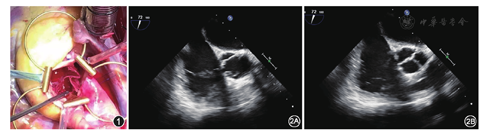

患者 男性,37岁,因"体检发现心脏杂音"于2016年7月1日入住吉林大学第一医院心脏外科。无高血压、糖尿病及传染病史。入院后体检:体温36.6 ℃,脉搏66次/min,呼吸16次/min,血压126/75 mmHg(1 mmHg=0.133 kPa);平卧位,双肺未闻及干湿啰音,心前区无隆起,心尖搏动位于第5肋间左锁骨中线外约1 cm,于心尖部可触及震颤,心界略向左扩大,听诊心率66次/min,心律齐,主动脉瓣听诊区可闻及4/6级收缩期喷射样杂音;肝脾未触及,双下肢无水肿。入院后实验室检查未见异常,胸部X线片未见异常;心电图提示窦性心动过缓。超声心动图提示:主动脉瓣重度狭窄合并轻度关闭不全;主动脉瓣瓣上峰值流速509 cm/s,肺动脉压103 mmHg,平均跨瓣压差67 mmHg;左心室舒张末期内径56 mm,射血分数61%。术前诊断:心脏瓣膜病,主动脉瓣重度狭窄合并轻度关闭不全,心功能(纽约心脏病协会分级)Ⅱ级。于2016年7月7日在全身麻醉下行主动脉瓣置换术。患者取平卧位,行胸骨正中劈开,分离心包外多余组织,纵行裁剪出8 cm×9 cm大小的心包,将心包放入0.6%戊二醛溶液中固定10 min,后于0.9%氯化钠溶液中洗涤3次,每次6 min。常规建立心肺转流后,当鼻咽温降至35 ℃时,阻断升主动脉,主动脉根部灌注停跳液,于主动脉根部上左右横行切开主动脉。切除主动脉三个瓣叶,用手术专用瓣叶测量器测量新瓣叶大小,右冠状动脉窦、左冠状动脉窦、无冠状动脉窦分别为27、23、25 mm。用专用模板在心包上标记各新瓣叶边缘线,分别裁剪出各瓣膜。首先行右冠状动脉窦瓣膜重建,应用一根5-0不可吸收缝线于心包片中点向左冠状动脉窦与无冠状动脉窦交联处缝合,另一半由心包中点向左冠状动脉窦与右冠状动脉窦交联处缝合,缝至交联处时垂直穿出主动脉壁,其余瓣叶缝法同前,然后应用2根4-0不可吸收缝线双头针呈倒梯形垂直穿出主动脉,将心包的瓣角组织固定在主动脉壁上,主动脉壁外行毛毡片打结固定,缝至交联处的5-0不可吸收缝线也在另外一个毛垫片上打结固定。瓣叶重建完成后(图1)注水实验示瓣叶对合良好。心脏复跳后,术中经食管超声心动图示瓣叶开放关闭良好(图2),主动脉瓣微量反流。手术主动脉阻断时间与心肺转流时间分别为165 min和218 min。患者术后7 d痊愈出院,术后第3个月复查超声心动图示主动脉瓣开放关闭良好,微量反流,主动脉瓣跨瓣压差14 mmHg。